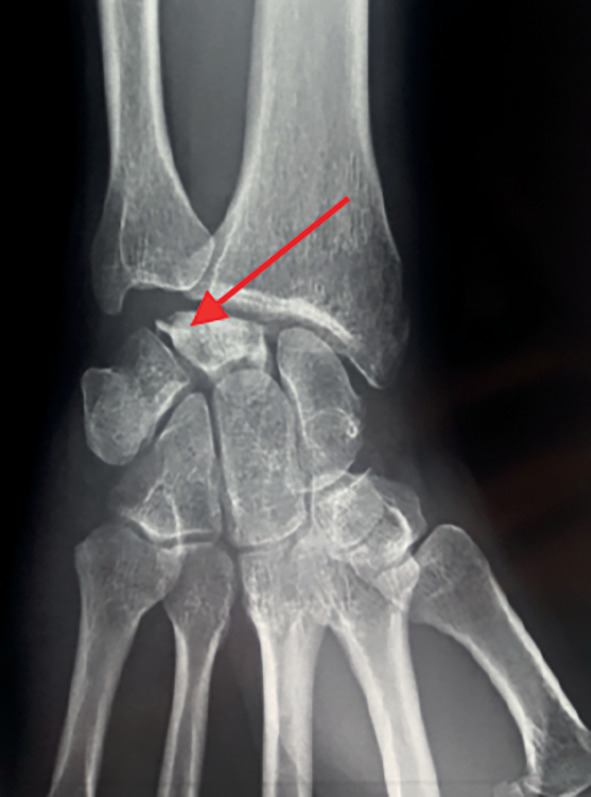

La radiographie montre une fragmentation partielle de cet os avec compactage osseux (fig. 1).